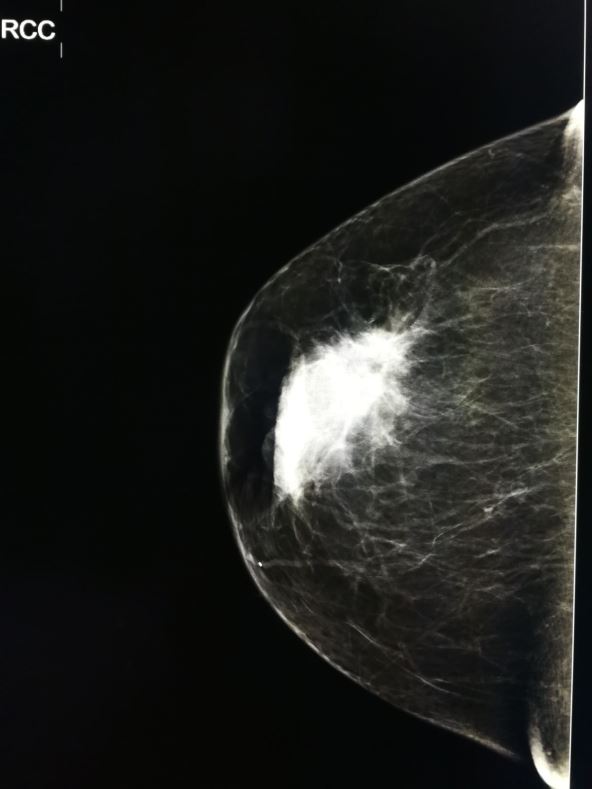

Lekari upućuju pacijentkinje na punkciju dojke kada prethodni nalazi, kao što su mamograf, ultrazvuk ili fizički pregled, ukazuju na prisustvo sumnjive promene. Posebno je indikovana za nalaze klasifikovane kao BI-RADS 4 (sumnjive promene) ili BI-RADS 5 (veoma sumnjive promene).

Njena dijagnostička tačnost je čak 92 procenta, što je čini izuzetno pouzdanom metodom za rano otkrivanje raka dojke, čak i kod promena manjih od jednog centimetra. Pored dijagnostičke svrhe, biopsija ima i terapijsku ulogu.